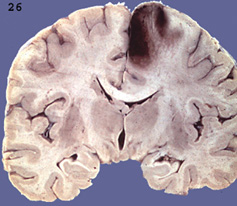

Question 21: The illustrated lesion is most likely caused by:

Correct. The lesion is a hemorrhagic infarct in the ACA territory,

most likely caused by embolism.

Incorrect. The lesion is a hemorrhagic infarct in the ACA territory, most likely caused by embolism.

Incorrect. The lesion is a hemorrhagic infarct in the ACA territory,